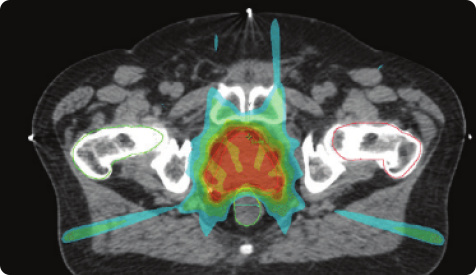

前列腺疾病防治&康复

前列腺疾病科

前列腺疾病防治&康复:​1.智能早期诊断体系2.微创手术诊疗体系3.前列腺术后快速康复管理4.前列腺微创手术尿控功能恢复体系5.前列腺微创手术性功能保护体系